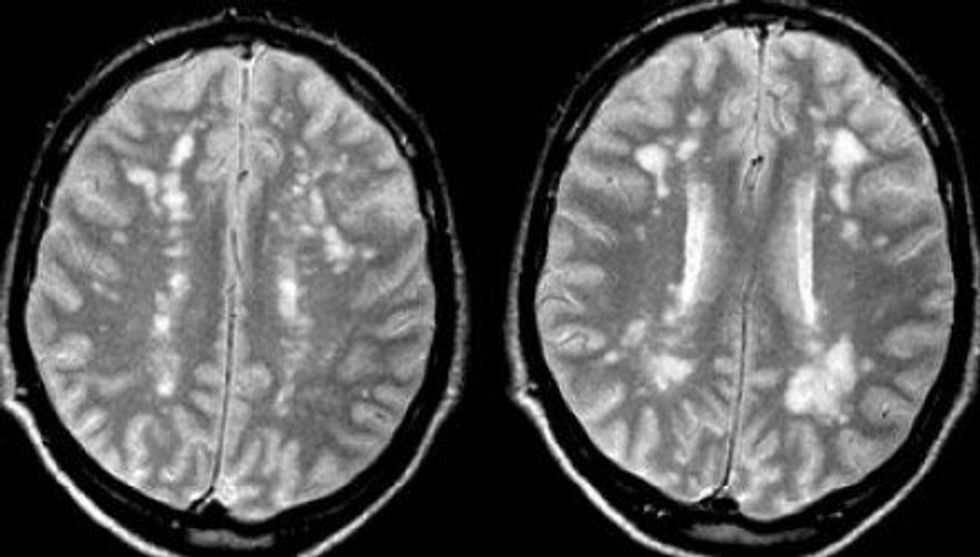

Finally, after analyzing results, doctors diagnosed my mom with Multiple Sclerosis, or MS. MS is a disease of the nervous system that disrupts the flow between the brain and the body. The disease causes crippling disabilities among many of its victims. As the doctor explained the MRI results, he described a classic cluster of lesions in the brain, typical in people who have MS.